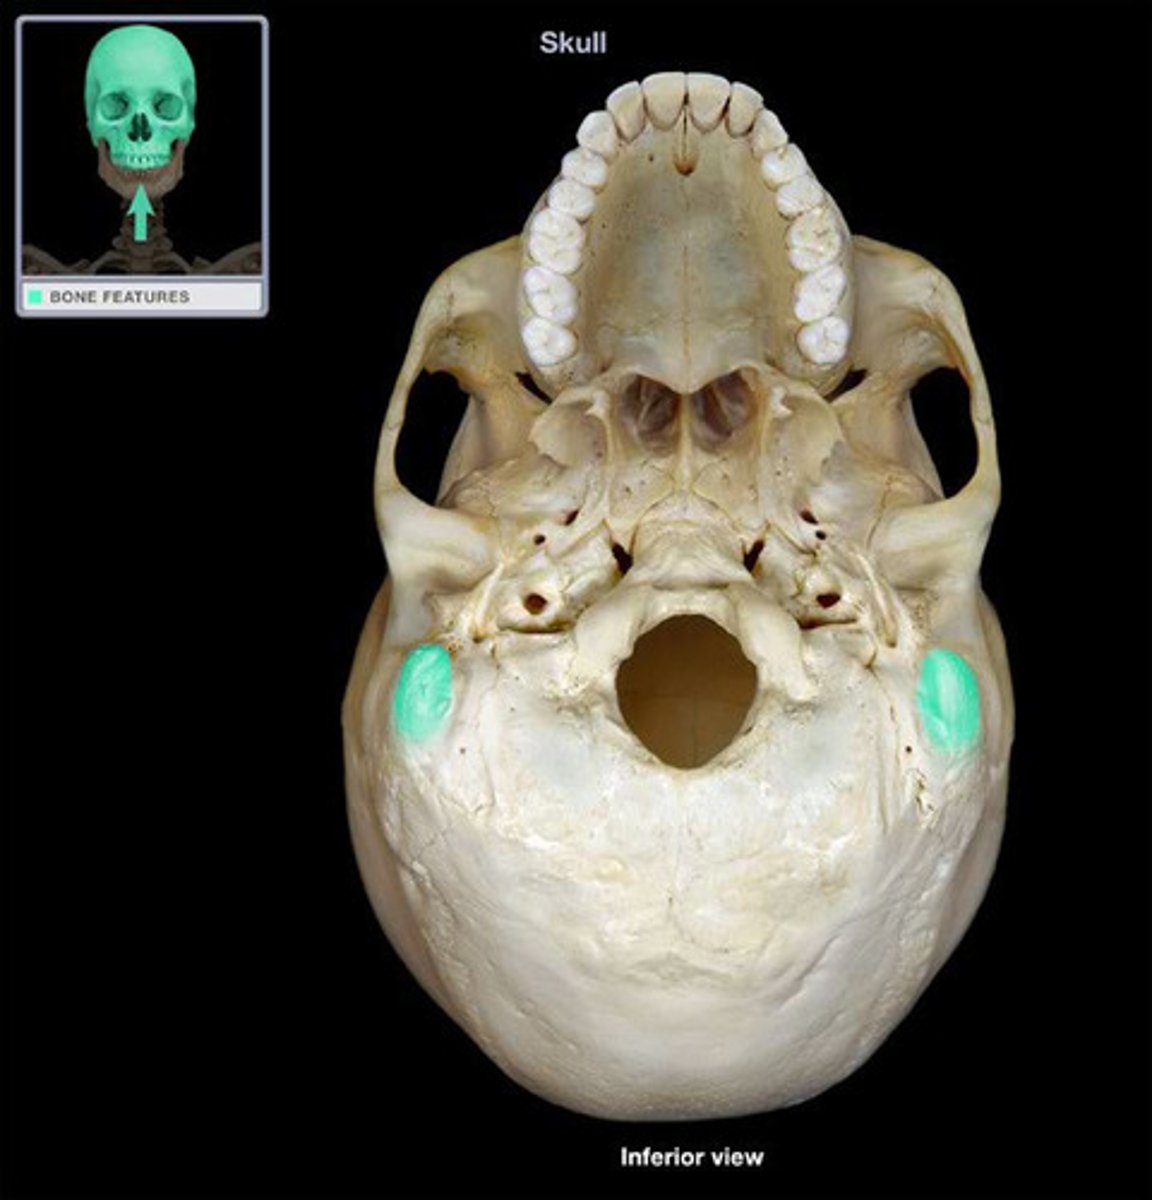

Occipital Bone

Condyles

Foramen Magnum

Jugular Foramen

Jugular Foramen

External Occipital Protuberance

Superior nuchal line